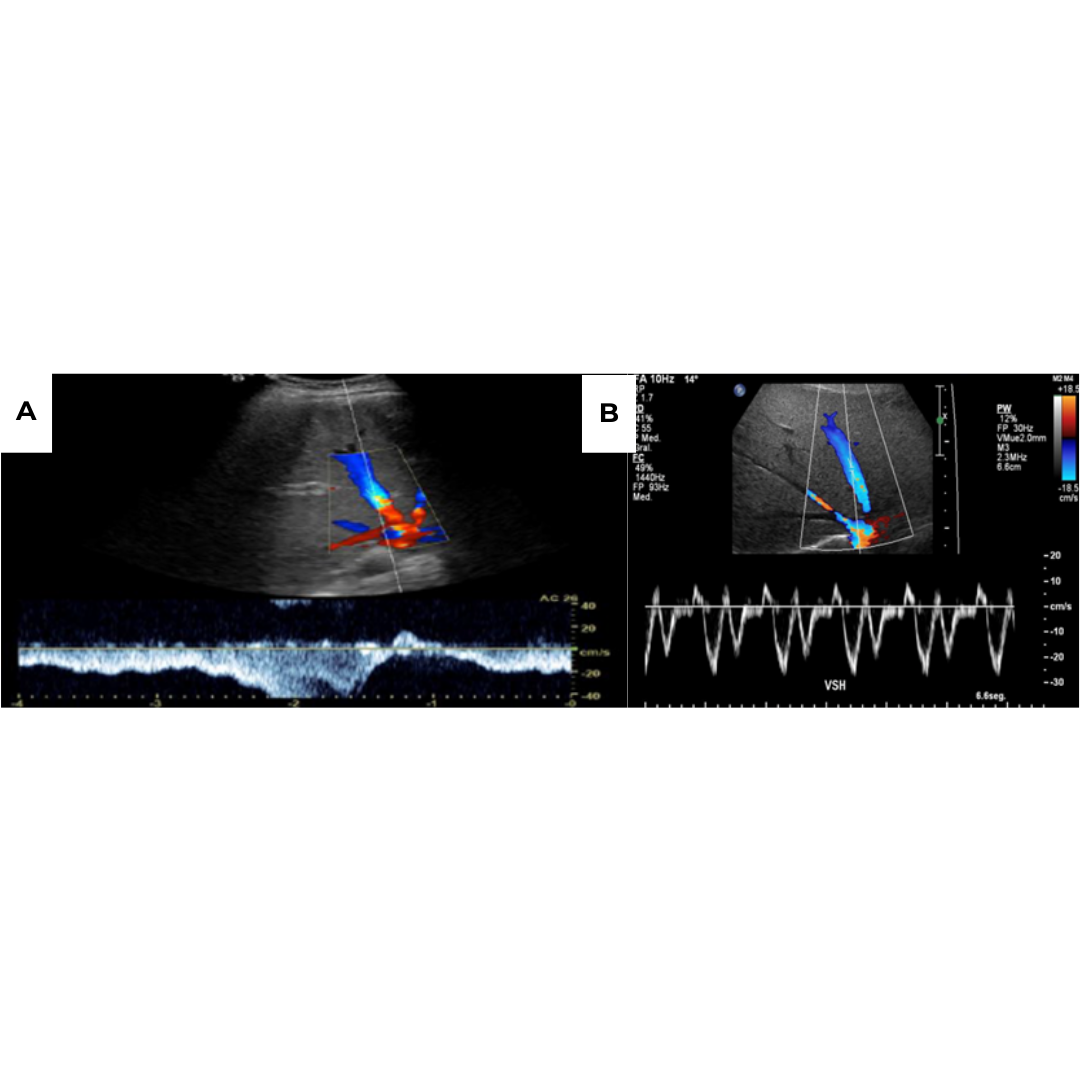

En las venas intrahepáticas al estudio espectral se visualiza un cambio de su morfológica típica trifásica, existe un aplanamiento o incluso morfología pseudoportal viéndose un flujo de aspecto bifásico por consecuencia de la estenosis que generan los nódulos de regeneración (figura 9).

Figura 9: A. Aplanamiento de la onda de la vena hepática media con pérdida del flujo trifásico a flujo bifásico. Flujo trifásico normal de venas suprahepática.